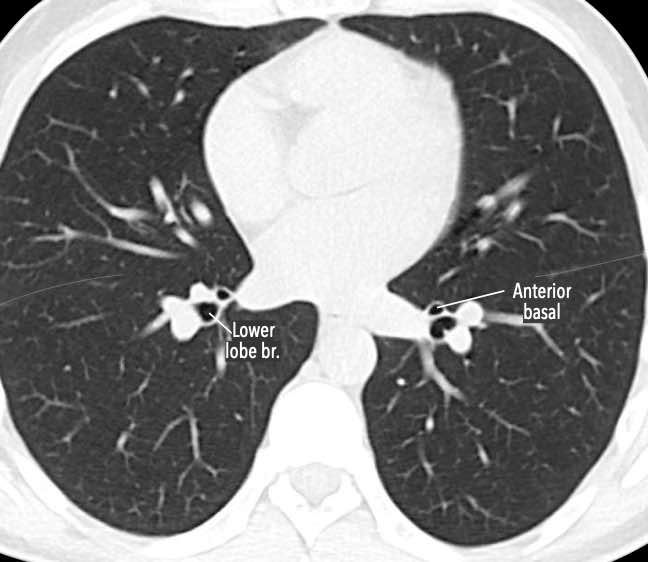

Phế quản trên CT

Cuộn qua các hình ảnh để quan sát khí quản phân chia thành phế quản chính phải và trái, sau đó tiếp tục phân chia thành các phế quản thùy và phế quản phân thùy.